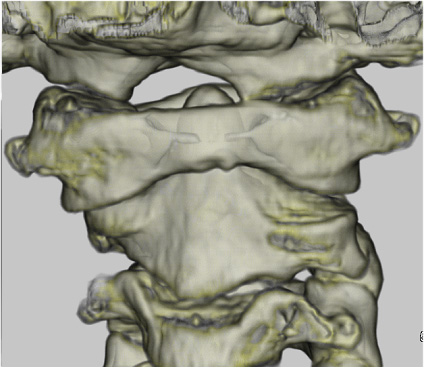

環軸椎回旋位固定

軽い外傷,咽頭周囲の炎症,手術などをきっかけとして第1,第2頚椎の間で回旋が起こり疼痛や緊張も相まって固定してしまう疾患です。コマドリ肢位と言われる頚部を曲げつつ回旋させた形で頚が固定され痛みのため動かせなくなることが多くみられます。まれですが頭頚部の病変が原因となっていることがあります。疾患そのものや治療があまり知られておらず,診断や治療が遅れると治療が困難になります。

・治療法

発症から1週間以内であればカラー固定や鎮痛剤の内服などで改善することが多く,容易に治癒しますが,1か月以上経過した場合は第2頚椎の関節面が変形してしまっていることが多く入院による牽引治療が必要となります。頚部がまっすぐになり疼痛無く対称に動かせるようになるまで牽引を行い,整復されれば骨の変形が改善されるまでは装具による維持を行います。